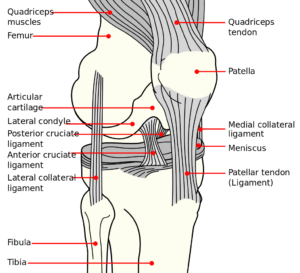

The knee joint contains two menisci (sing.: meniscus), which are crescent-shaped fibrocartilage structures composed largely of collagen, fibroblasts and chondrocytes. The collagen is arranged in longitudinal, circumferential bundles and also interwoven in radial and oblique directions to withstand force. Meniscus is derived from the Ancient Greek word miniskos meaning ‘crescent’. Menisci are also found in the wrist, acromioclavicular, sternoclavicular and temporomandibular joints and play key roles in joint stability. Each knee contains a lateral and a medial meniscus, that unlike articular discs, cover only part of the articulating bones, but similarly provide structural support. Mensci reduce friction, support load, absorb shock, guide range of motion, and provide proprioception. Menisci are wedge shaped and composed of “red” and “white” cartilage, with the red outer portion being more vascularized than the white portion and therefore more adept at healing. It has been found that vascular perfusion diminishes after the age of 40. Nerve endings within the menisci are thought to play a role in providing sensory feedback and proprioception.

- Cartoon illustrates red zone (well vascularized) and white zone (less blood vessels)

- Knee cartilages function as shock absorbers and guide range of motion

- Terrible triad: tear in MCL, ACL, and medial meniscus (common in soccer)

- Knee © Mysid is licensed under a Public Domain license